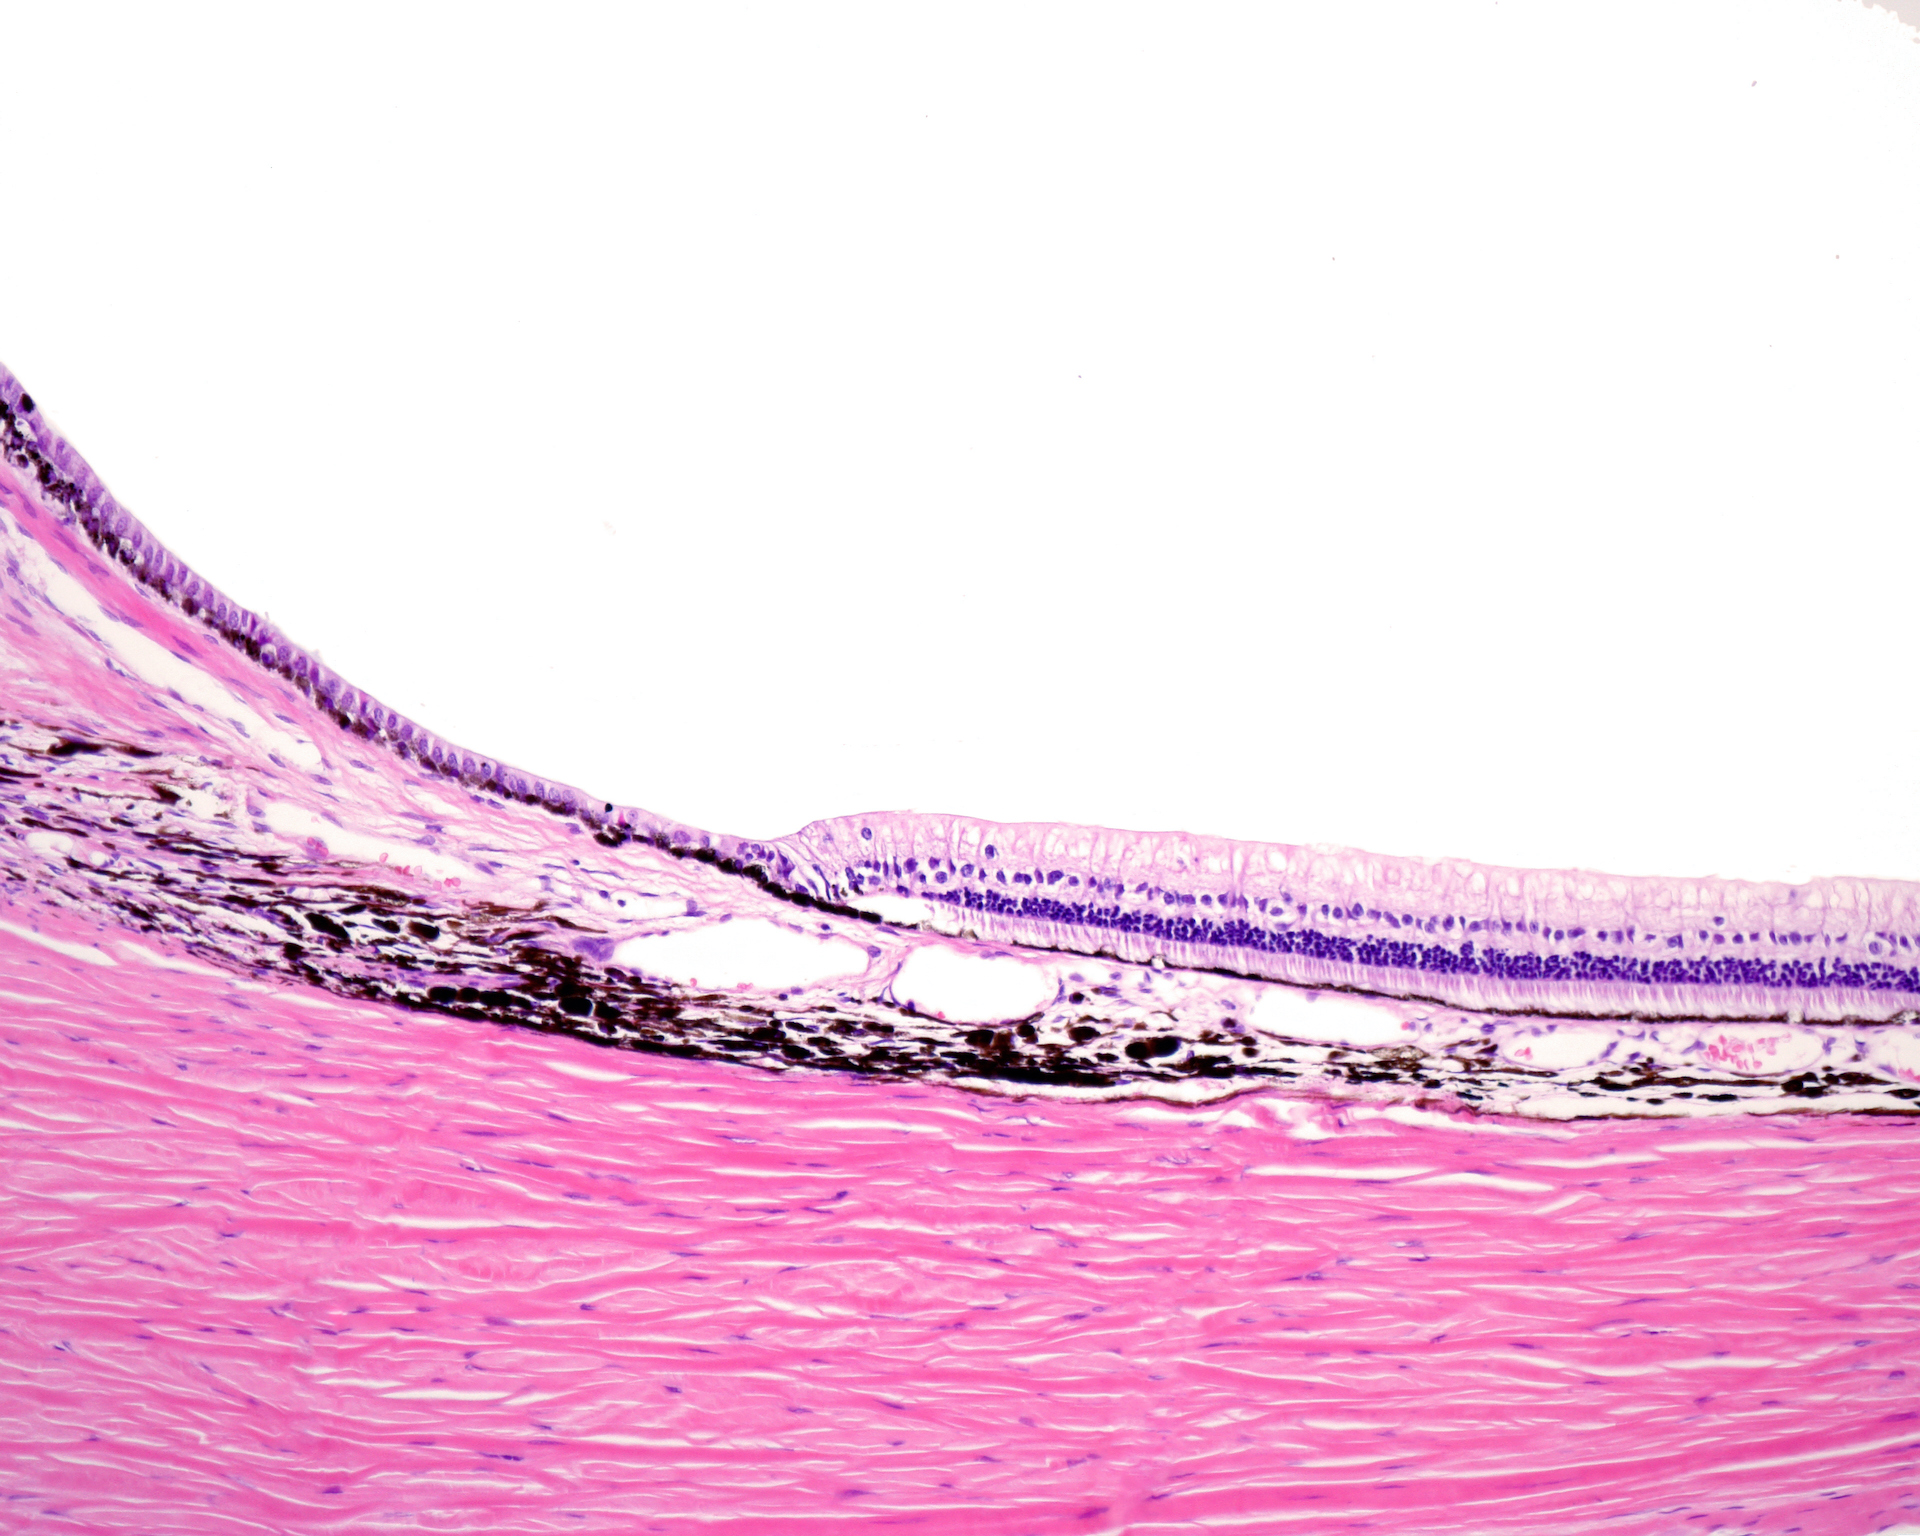

Retinal pigment epithelium hypertrophy. Download Scientific Diagram

Retinal pigment epithelium hypertrophy. Download Scientific Diagram What Is Retinal Pigment Epithelium The retinal pigment epithelium (rpe) is a monolayer of cells located at the posterior of the eye, between the retina and choroid, which. The retinal pigment epithelium is a single layer of epithelial cells based on the bruch's membrane, and with the apical surface covered with. Individual rpe cells are tightly joined to their neighbours, producing an effective barrier that. What Is Retinal Pigment Epithelium.

The basic retinal structure. Histological appearance of choroid and What Is Retinal Pigment Epithelium The retinal pigment epithelium (rpe) between retinal photoreceptors and choroidal capillaries is a single layer of cells. The retinal pigment epithelium (rpe) is a monolayer of cells located at the posterior of the eye, between the retina and choroid, which. The retinal pigment epithelium (rpe) is an specialized epithelium lying in the interface between the neural retina and the. The. What Is Retinal Pigment Epithelium.